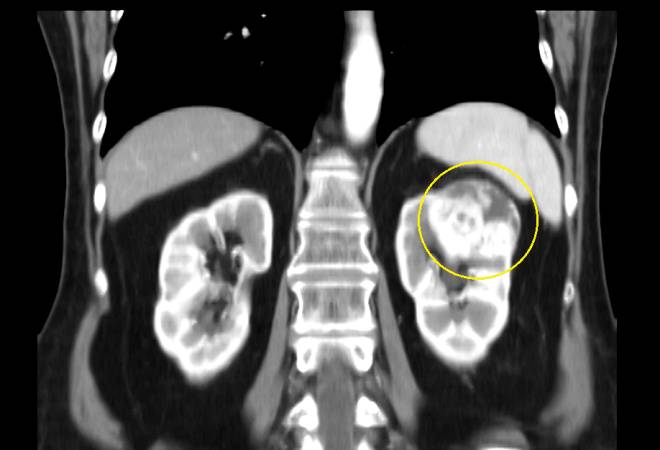

Паренхиматозная киста левой почки представляет собой доброкачественное образование, заполненное жидкостью, которое возникает в тканях почки. Врачи отмечают, что такие кисты могут быть бессимптомными и часто обнаруживаются случайно при ультразвуковом исследовании. Однако в некоторых случаях пациенты могут испытывать дискомфорт в области поясницы, а также боли, которые могут иррадиировать в бок или живот.

С возрастом почки теряют часть здоровых тканей, становятся слабее и хуже фильтруют жидкость, легко подвергаются воспалительным процессам и инфекционным заболеваниям. Именно на ослабленных почках и начинают формироваться кисты паренхимы правой почки или левой стороны органа. Кисты представляют собой небольшие мешочки или капсулы из мягкой ткани, которые заполняют полости или поврежденные впадины на почках и формируются там, прикрепляясь каналами или жгутиками к здоровым частям органов.

- Патологией кисты почек принято считать ее аномальное увеличение в размерах. Медицине известны случаи, когда паренхиматозная киста достигала 10 и более сантиметров в диаметре. Паренхиматозная киста левой почки что это такое, когда опухоль увеличивается? При таких размерах киста гарантированно нарушает работу внутренних органов, приводит к воспалениям и инфекционным заболеваниям органов брюшной полости.